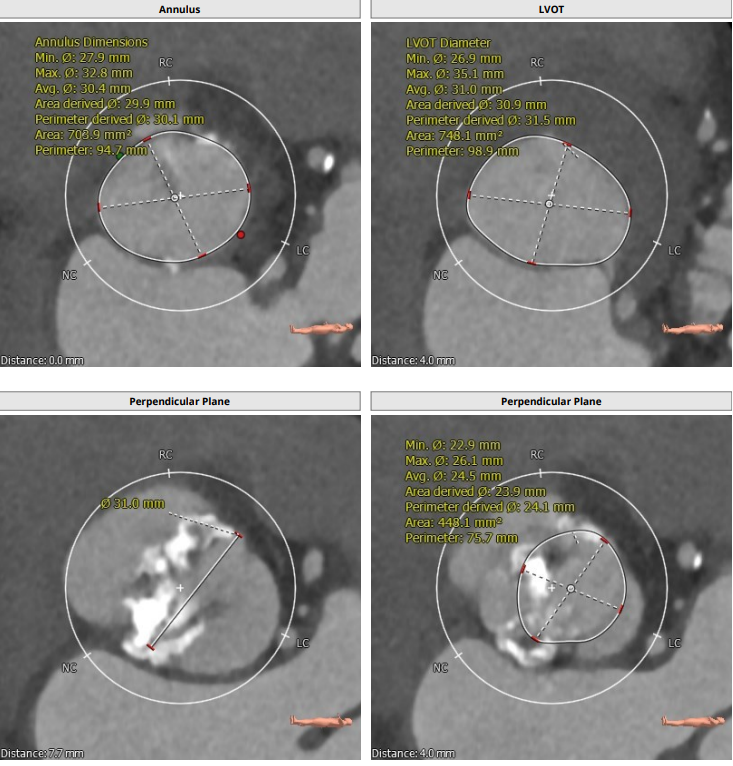

本例患者只有61岁,超声诊断低流速低压差AS,合并升主动脉扩张,CT下测量升主动脉超过50,原则上首选外科手术。但广东省人民医院大血管组会诊后考虑患者低流速低压差,行主动脉瓣和升主动脉置换术,手术风险极高,建议TAVR。从解剖上,瓣环流出道的大小分别是30、31,但瓣上结构是TYPE 0二叶瓣,重度钙化,联合部有钙化融合,瓣上短轴31,窦高度超过23,横位心,角度78°二叶瓣方向呈1点到7点方向。这种解剖做TAVR无疑挑战极大。对于低流速低压差的患者合并解剖挑战的病人,术前计划就是ecmo辅助下TAVR。考虑二叶瓣和重度钙化,目标瓣膜是29号,故用23号球囊预扩,尽量不破坏瓣上结构,另外考虑横位心,升主宽,破裂风险高,瓣膜跨瓣困难,故准备抓捕器辅助跨瓣。投照角度方面准备了瓣膜切线位(左肩),用来跨瓣和球扩,同时准备多一个右足位,这个角度下瓣环和人工瓣膜可以达到共平面,方便瓣膜定位。因为升主宽,横位心,主动脉迂曲,为减少破裂风险,没有选择plus。术中跨瓣遇到较大挑战,因为主动脉根部的角度大,普通的AL2,JR2,多功能导管均无法跨瓣,尝试直头导丝和弯头泥鳅也失败,最后是JL4加直头导丝成功跨瓣。预扩后瓣膜跨瓣尽管在抓捕器辅助下仍然非常困难,在反复尝试后侥幸跨瓣。瓣膜释放后位置偏深,但结合瓣膜角度,瓣周漏可以接受,压差消失,故未再行瓣中瓣。术中未发生停跳,故手术结束后撤去ECMO返回CCU。术后一个月随访EF值明显改善,患者自我感觉明显好转,虽然有中度瓣周漏,但是患者年轻,调整好心功能后,为以后外科置换升主动脉和主动脉瓣打下基础。

患者为type0二叶瓣,重度钙化,78度大横位心,左心明显扩大,EF值为21%,瓣环径为30.1,LVOT31.5,二叶瓣鱼嘴开口初短径为31,钙化融合至对侧为27.5,左右冠高度均为25.7,升主明显扩张。